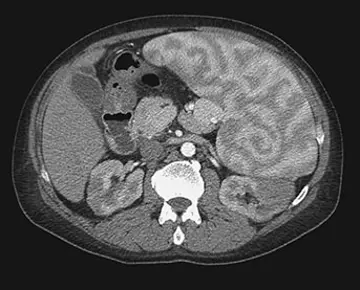

رادیولوژی - صفحه 3